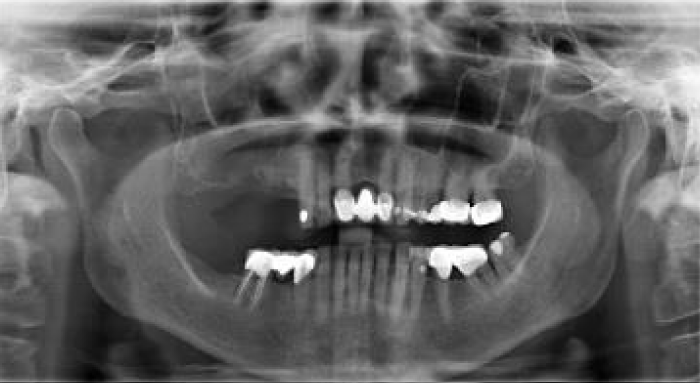

The radiographic examination using an orthopantomogram showed few teeth in the upper jaw with severe vertical resorption in the right premolar and molar regions. In the lower jaw, there is a moderate vertical bone resorption and no teeth present (Figure 2).

Figure 2: Shows the panoramic radiograph of the patient at presentation.